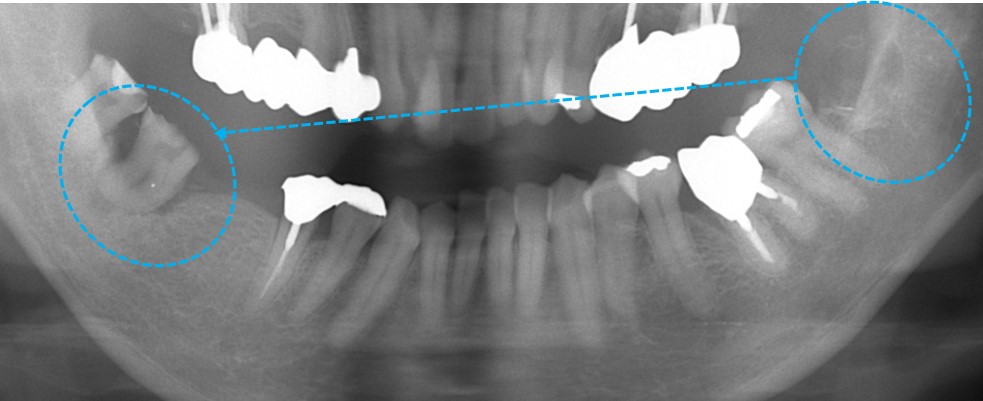

オレンジ〇の歯が重度の歯周病で抜歯適応となりました。

青〇の親知らずが浮き上がってきており、この親知らずも抜歯適応です。

しかしながら、この親知らずをただ抜歯するだけでは勿体ないので、オレンジ○の歯を抜歯した後に移植することにしました。